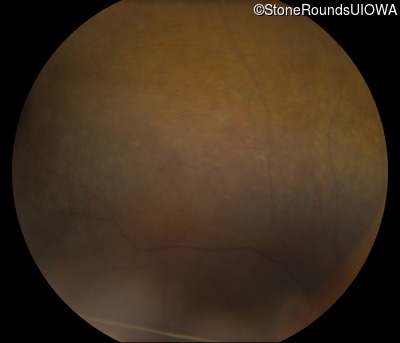

Fundus Photography - Right - 20/50 -3

Exemplar